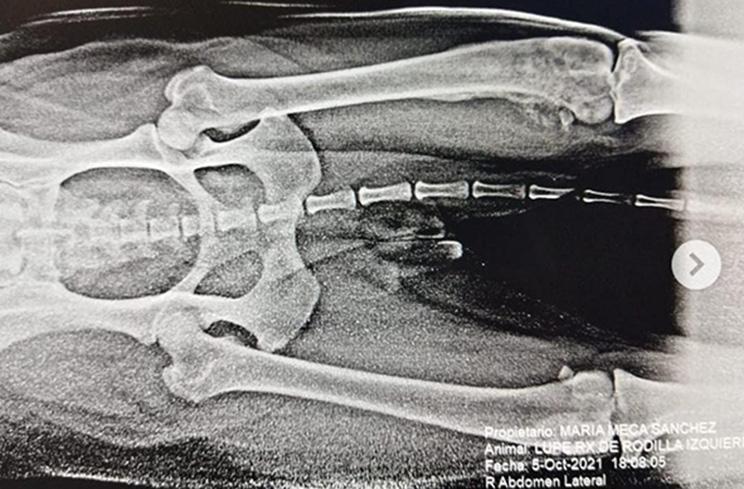

Aquí les dejo 4 imágenes de la paciente llamada Lupe, con 7 años de edad! Que presentó un osteosarcoma del miembro posterior izquierdo (pata trasera) y metástasis a nivel de tórax.

La propietaria de la paciente, decide llevar a Lupe a su veterinario de confianza porque de manera inesperada comenzó a claudicar (cojear) de esa pata trasera.

El veterinario al hacer la revisión física detecta que esa pata (a nivel de la rodilla) está inflamada y con dolor, él manda analgésicos y a su vez remite a la paciente a hacerle una radiografía del miembro posterior izquierdo, (pensando que podía tener ruptura del ligamento cruzado), es ahí cuando llega a mi consulta y le elaboro el rx (que el colega pidió hacer), al realizarla se detecta que es un osteosarcoma, por faltas económicas no se le realiza la radiografía de tórax el mismo día que se le realizó la del miembro trasera.

Una semana mas tarde se le realiza la radiografía de tórax y también se confirma que tiene metástasis la perrita, no se le dio ni 6 meses de vida, ya que la paciente estaba presentando una fuerte tos, en menos de un mes la paciente le costaba incorporarse por sí sola, no estaba tan activa y la tos se frecuentó más, a parte al toser expulsaba algo de sangre. La propietaria decide sacrificarla.